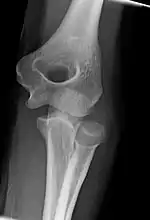

Left: Lateral X ray of a dislocated right elbow

Right: AP X ray of a dislocated right elbow